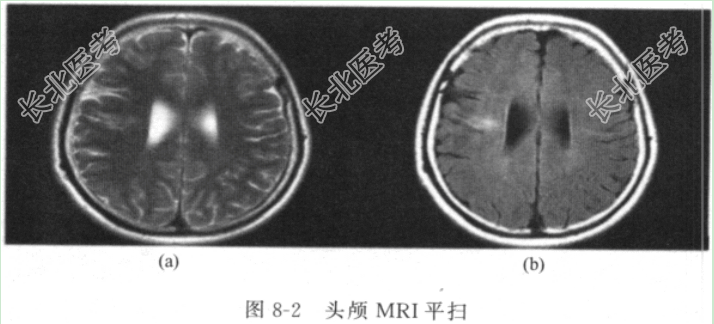

- [材料题] 【病历汇报】患者,女性,16岁,主因“反复发作性意识丧失、四肢强直10年余”入院。患者2005年9月曾患病毒性脑炎,当时表现为发热、头痛、恶心、呕吐,无肢体瘫痪、肢体抽搐、意识丧失等。当地医院予更昔洛韦及甘露醇治疗,患者症状逐渐好转。出院后患者出现言语减少,发音吐字不清,反应迟钝。2006年3月起患者出现发作性意识丧失,呼之不应,头、眼向侧偏转,四肢抽搐,偶伴喊叫、小便失禁,发作后不能回忆发作当时的情况,伴有嗜睡、肌肉酸痛,每月发作6~8次,每次持续3~8min。患者就诊于当地医院,查脑电图示双侧较多散在和阵发θ波及尖波、尖慢波。当地医院予丙戊酸钠每次0.5g、2次/日治疗。服用丙戊酸钠后,患者发作稍有减少,每月仍有2~3次发作。后加用卡马西平每次0.2g,3次/日,患者发作次数明显减少,每6个月发作1~2次。2012年7月,患者自行减少抗癫痫药物用量,常有漏服,发作频率明显增多,每月发作8~9次,每次发作持续2~3min。患者于2012年9月12日就诊于当地医院,予卡马西平每次0.4g、2次/日,丙戊酸钠每次0.5g、2次/日治疗。2015年6月20日患者入院就诊,诉近1年内每月仍有5~6次发作。患病以来患者记忆力、理解力减退,发音吐字不清,情绪反应幼稚化,偶有冲动、打人。现为进一步诊治收入院。护理检查体温37℃,呼吸20次/分,心率80次/分,血压116/76mmHg。早期预警风险评分(MEWS)1分,神志清楚,查体欠配合,对答部分切题。两侧瞳孔等大等圆,对光反射灵敏。颈软无抵抗、心、肺未见明显异常。四肢肌力正常、肌张力正常,腱反射对称存在,病理征未引出,共济可。辅助检查脑电图(图8-1)示:双侧较多散在和阵发高幅θ波、δ波、尖波,右侧更明显,深呼吸后明显增多。头颅MRI平扫(图8-2):双侧额颞叶异常信号,局部脑萎缩。海马MRI平扫(图8-3)未见明显异常。血药浓度:丙戊酸63.14μg/mL,卡马西平8.76μg/mL。